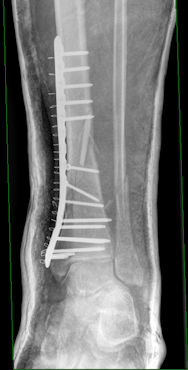

Eine Bergtour auf den Stubwieswipfel (1.786 m) im Toten Gebirge ändert den Zeitplan abrupt (sic!): 50 Höhenmeter unter dem Gipfel, immerhin im Abstieg, das Gipfelglück war mir noch vergönnt, breche ich mir den Unterschenkel. Was folgt sind Taubergung, Hubschrauberflug und Schockraum. Gibt es nach einem ersten Röntgen noch Hoffnung, dass ich einige Tage nach der Operation wieder belasten darf, sieht es nach dem CT anders aus: Es ist ein komplizierter Spiraltrümmerbruch von Schien- und Wadenbein, der auch nach der Verplattung und Verschraubung zumindest sechs Wochen nicht belastet werden darf. Wir peilen Mitte August für unsere Abreise nach Skandinavien an.